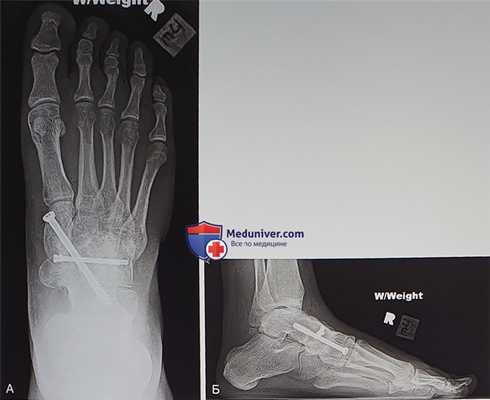

- Со стороны медиальной клиновидной кости в таранную кость вводится длинный канюлированный винт, обеспечивающий значительную стабильность и компрессию (рис. 10)

- Еще одним вариантом фиксации является использование нескольких небольших винтов и/или пластин. Тыльные пластинки, однако, будут ощущаться под кожей и после формирования костного блока нуждаются в удалении